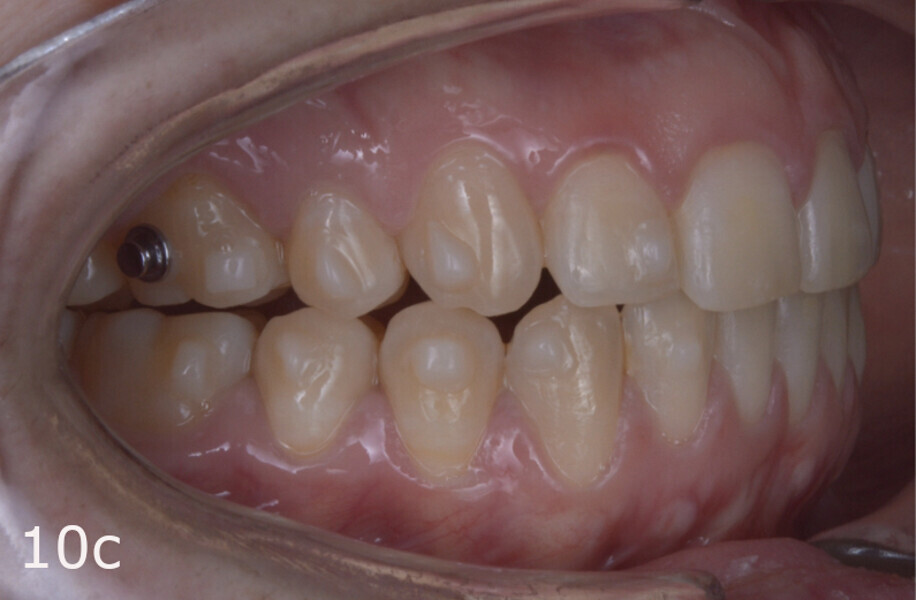

The treatment objectives included closing the anterior open bite, achieving a bilateral Angle Class I relationship and a proper overjet and overbite, correcting the midline discrepancies, and achieving a profile harmonisation. The treatment plan consisted of orthodontic camouflage treatment with asymmetric distalisation in three of the four quadrants using Invisalign aligners (Align Technology) and third molar extraction. The Invisalign Comprehensive package was chosen, and 63 pairs of aligners were used (Figs. 7–10). Each aligner was worn for 20 hours a day for one week each. The use of Class III elastics on both sides was indicated. Afterwards, ten refinement aligners were needed to improve the interdigitation on the right side (Figs. 11 & 12).